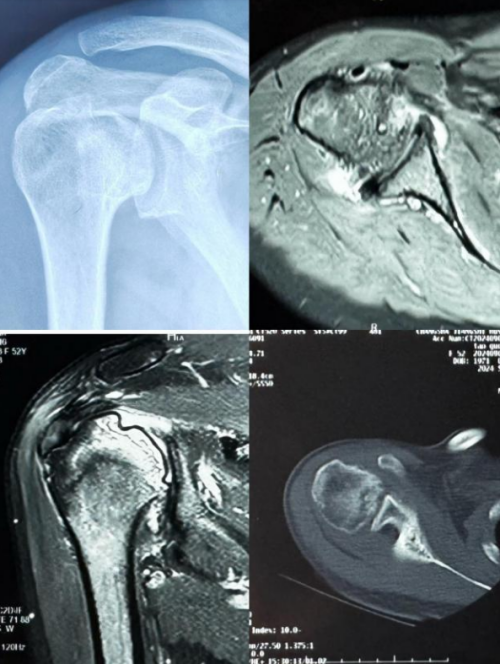

患者术前评估:右上肢无法正常上抬

术前影像检查显示肱骨头软骨下骨囊性变,肱骨头塌陷